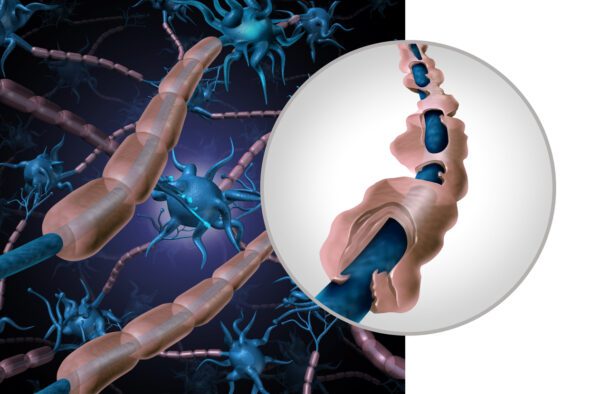

Iedere zenuwcel kan met ongeveer 5.000 andere zenuwcellen verbinding maken

De hersenen zijn opgebouwd uit 86 miljard zenuwcellen en 1000 miljard gliacellen

Luister nuWij, hersenonderzoekers, willen het brein nog beter begrijpen en zo doorbraken realiseren in de behandeling van ziektes als MS, Parkinson, Alzheimer en depressie. Om onze missie te volbrengen, willen wij ons volledig concentreren op ons onderzoek. Wil je ons daarbij helpen?